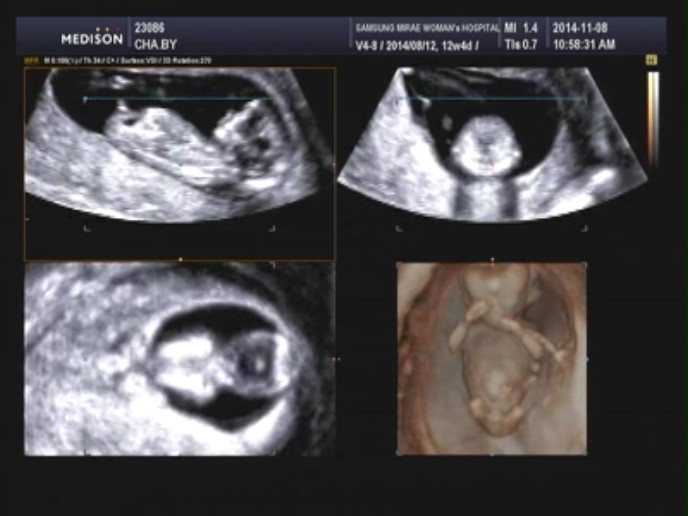

[12주 5일] 1차 기형아 검사 및 첫 입체초음파 :)

12주 5일, 1차 기형아 검사 및 첫 입체초음파 11월 8일! 거의 한달만에 오는 병원 방문일, ...